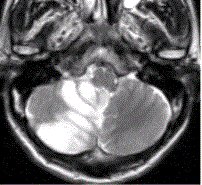

问题 患者女,75岁,突发偏瘫、头痛、头晕10h。既往有高血脂、糖尿病史。MRI表现如下图。 脑梗死的CT检查中,“模糊效应”出现于

选项 A.6h以内 B.24h以内 C.72h以内 D.14d左右 E.2~3周

答案 D